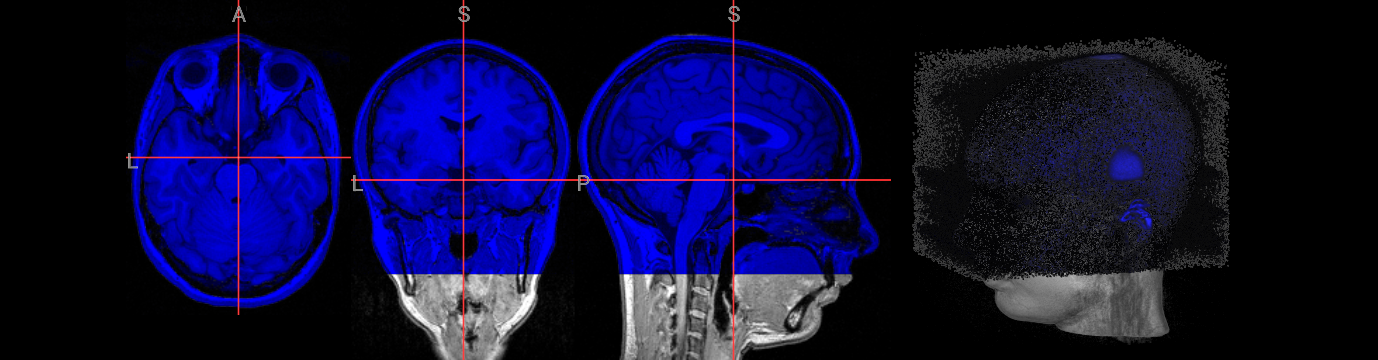

Brain extraction is a fundamental preprocessing step in neuroimaging analysis, particularly critical for structural image segmentation where precision matters most. While BET is straightforward to use, achieving optimal results often requires understanding how to fine-tune parameters for challenging datasets. This interactive version covers the core BET fundamentals, including parameter adjustment techniques for difficult images, and troubleshooting approaches for problematic cases. The hands-on format allows you to experiment with different settings and immediately see their effects on brain extraction quality.